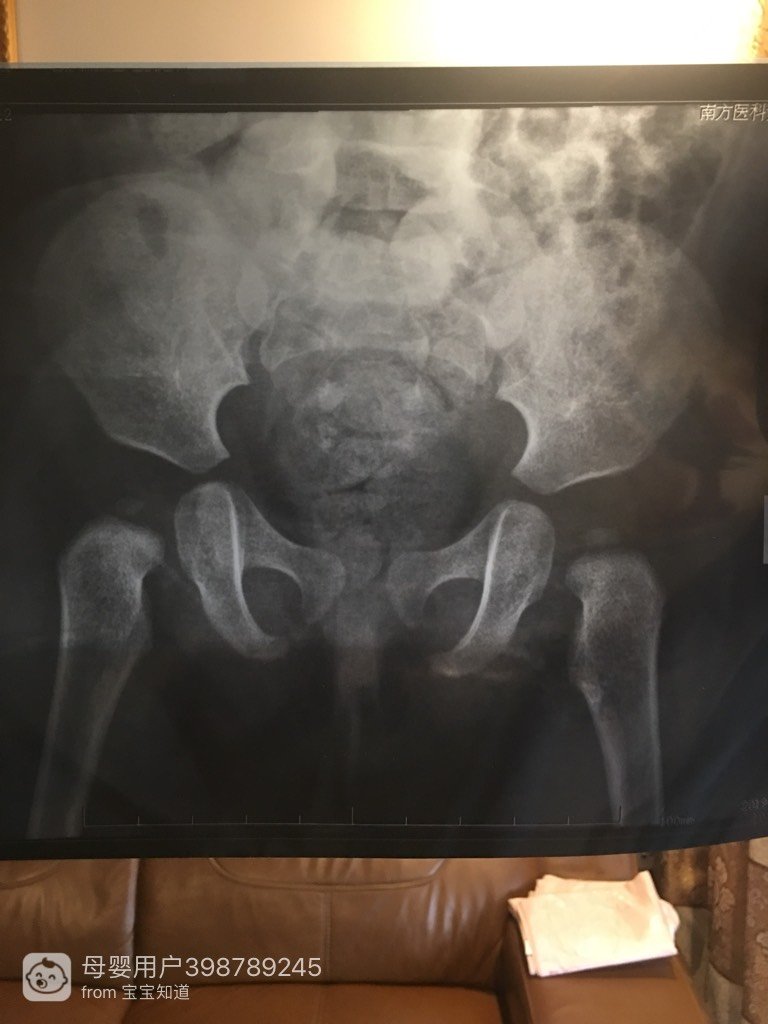

宝宝走路有问题

这是我家一岁宝宝的拍片,请问有人给婚寸解命报答一细苦实下吗?谢谢了